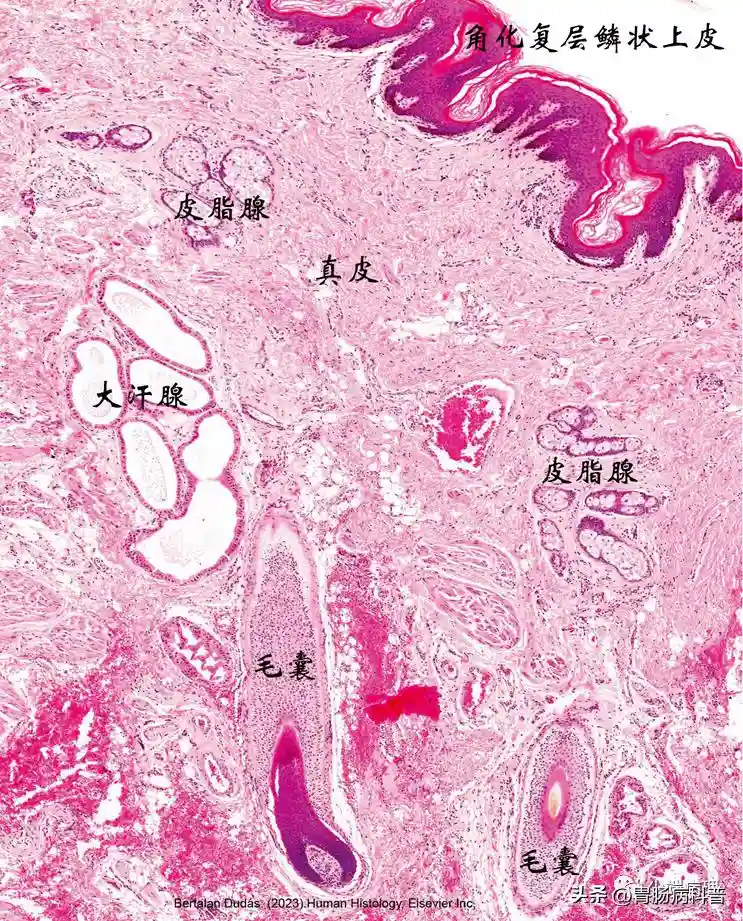

肛管皮肤区组织结构图

肛管的皮肤区被覆角化复层鳞状上皮,其下为不规则致密结缔组织真皮,并含有与毛囊、皮脂腺,还有大量的管腔扩张的大汗腺(肛周腺)。